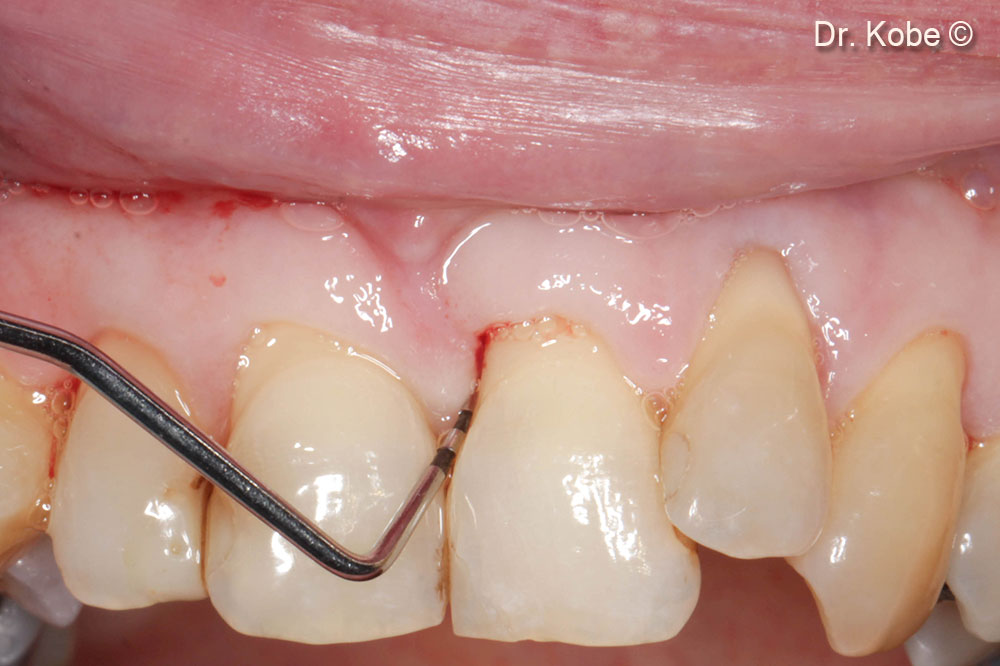

4. Access to the defect

5. Root scaling and debridement